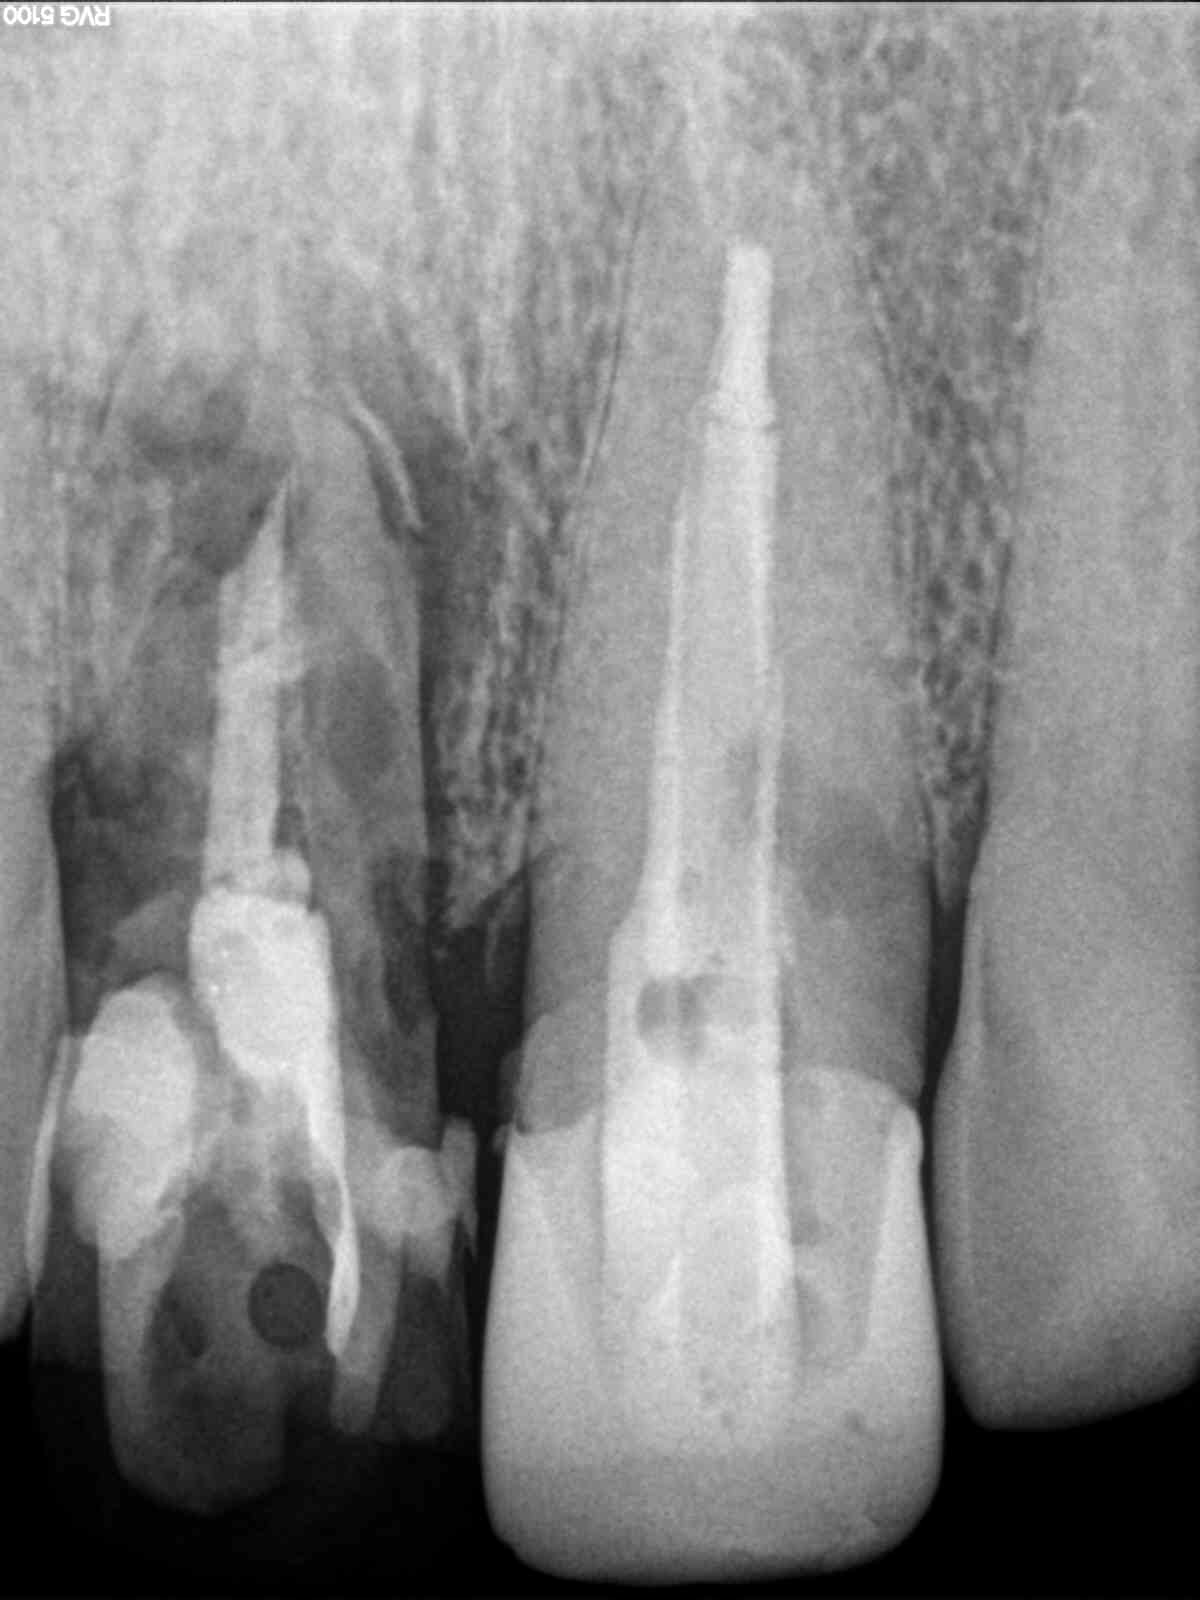

Este paciente llegó al consultorio con reabsorción dentinaria (pérdida de la estructura del diente). Por ello se le extrajo el diente, se le colocó un implante y se restauraron las piezas con coronas de cerámica pura.